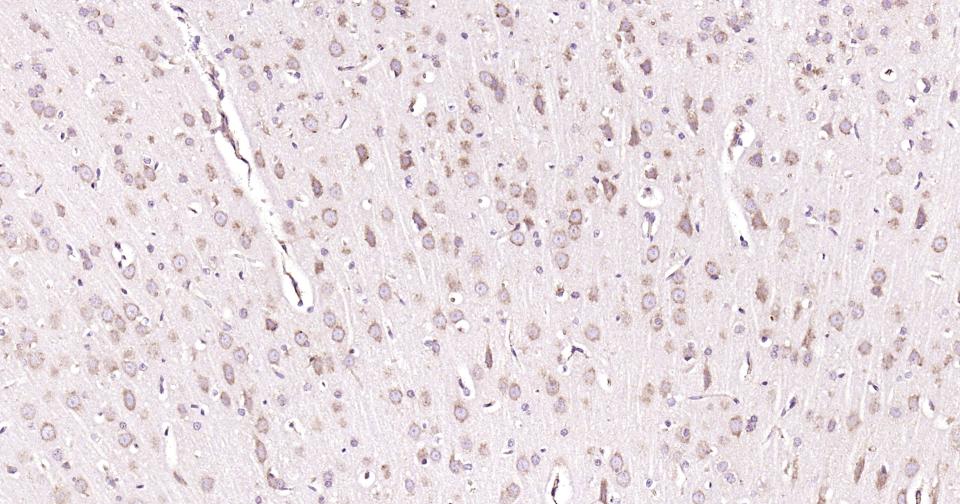

| 应用 | 已检合格种属 | 预测种属 | 推荐稀释比例 |

|---|---|---|---|

| IHC-P | Human, Mouse, Rat | 1:100-500 | |

| IHC-F | Human, Mouse, Rat | 1:100-500 | |

| IF | Human, Mouse, Rat | 1:100-500 |

交叉反应: Human, Mouse, Rat